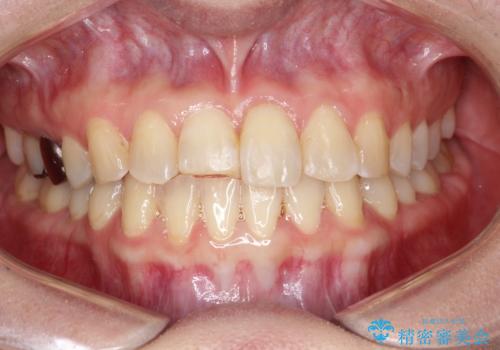

インビザラインにて矯正治療後の前歯のセラミッククラウン治療

- 前歯の歯並びが気になるとのことで来院されました。

右上の1番目の歯が内側に入り込んでしまっており、その歯がの先端がすり減ってしまっていました。

インビザラインによる矯正治療で前歯の歯並びを改善し、セラミッククラウン装着により歯の形態の回復をする計画としました。

矯正とセラミックを併用することで、より完成度の高い状態に仕上げることができました。